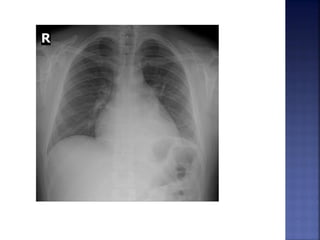

RAIO X DE TÓRAX

 Duplo contorno na silhueta direita do

coração.

 Sinal da bailarina (deslocamento superior do

brônquio fonte E).

 Abaulamento do 4º arco cardíaco esquerdo.

 Deslocamento posterior do esôfago

contrastado.

 Inversão do padrão vascular.

 Linhas B de Kerley.

 Edema intersticial.